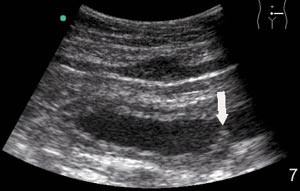

I 81 % av tilfellene fant vi tilfredsstillende bildekvalitet (e-fig 1) med bruk av mobil skanner, til tross for at det hos 28 % av pasientene var dårlig innsyn. Noen syntes at skjermen var for liten og at dette utgjorde en begrensende faktor. Et ultrasonogram hvor man sammenlikner opptak gjort på samme pasienter med Sonosite 180 mot Siemens Elegra demonstrerer hvor bra bildekvaliteten er (fig 2). Gjennomsnittlig tidsbruk under skanning var 7 ± 3 minutter. I 83 % av tilfellene ble den aktuelle kliniske problemstillingen adekvat besvart med mobil skanning, i fire tilfeller (11 %) ble det ansett som nyttig å skanne pasienten med et stasjonært ultralydapparat i tillegg. Utredning og/eller behandling av pasientene ble i 39 % av tilfellene endret som følge av skanning.

Undersøkerens totale tilfredshet med bruk av denne skanneren var: 0 lite tilfreds, 8 % litt tilfreds, 11 % moderat tilfreds, 36 % meget tilfreds, 45 % svært tilfreds. Skanneren var ikke bare egnet til «enkle» problemstillinger, men kunne også gi tilfredsstillende svar på mer kompliserte kliniske og bildemessige utfordringer (fig 3, fig 4).